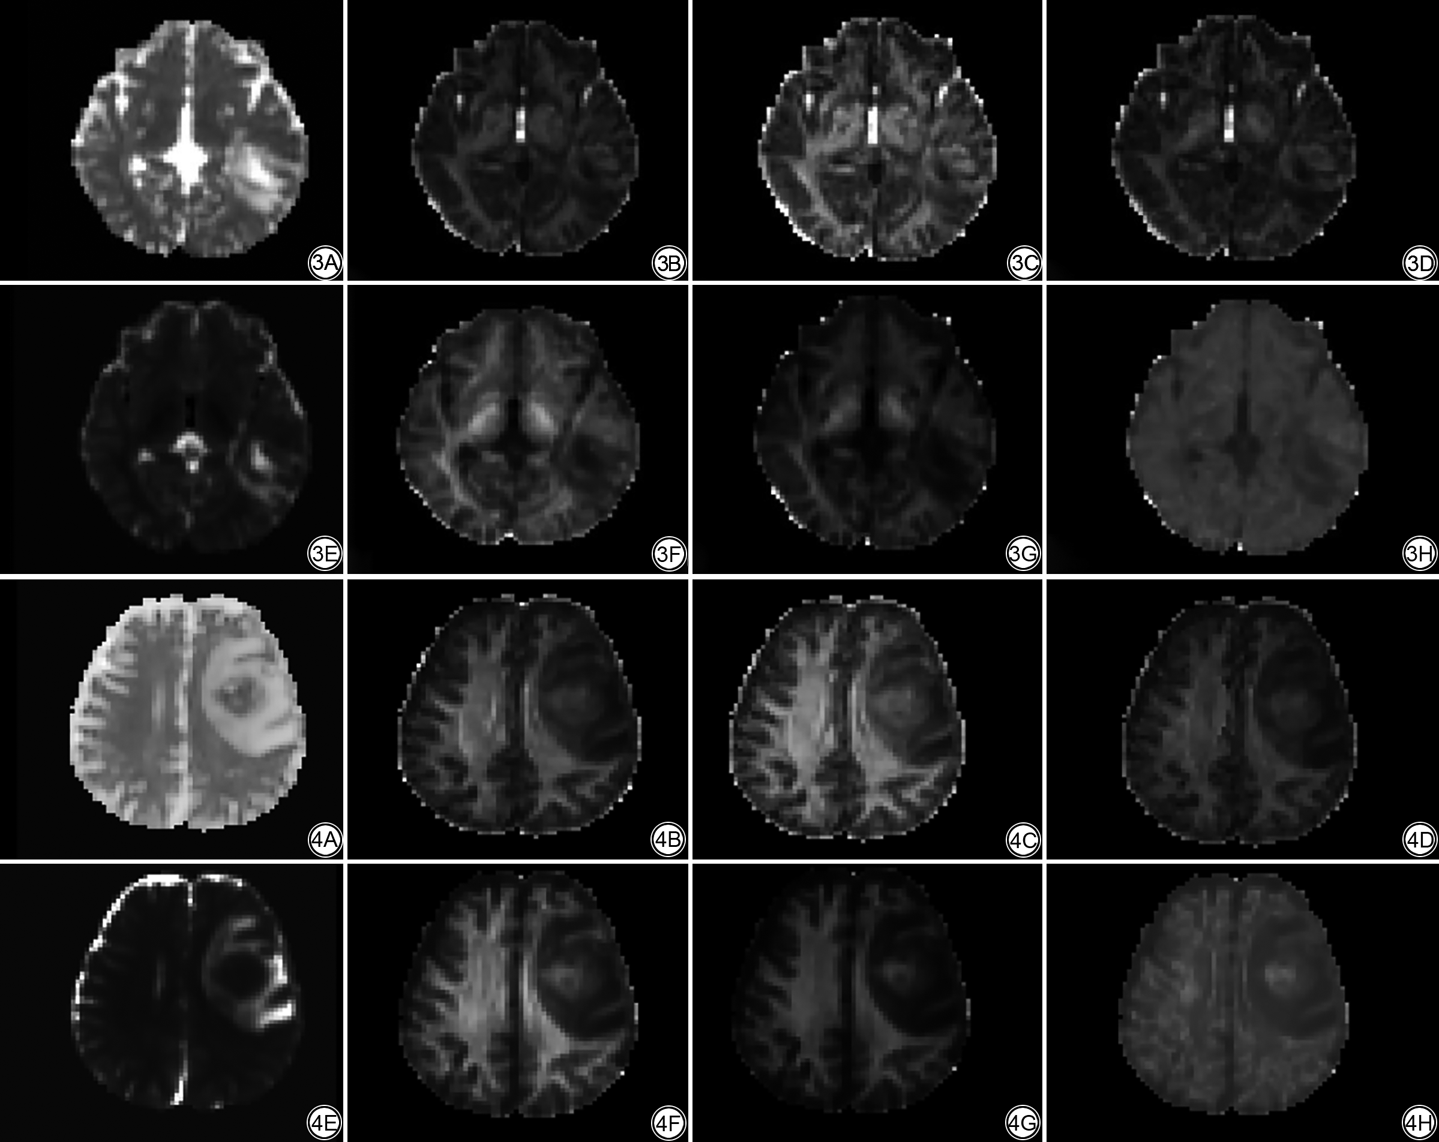

对于MAP-MRI参数,甲基化组的NG、NGAx、RTOP及RTAP值明显低于非甲基化组(P值均<0.05),而甲基化组的QIV的值明显高于非甲基化组(P=0.033;表3,图3、4)。

MAP-MRI作为一种新的空间数据获取分析模型,其对于脑组织的复杂微观结构改变更具有敏感性。在本次研究中,与MGMT非甲基化组相比,MGMT甲基化组具有更高的QIV值以及更低的NG、NGAx、RTOP、RTAP值。QIV被定义为q空间逆方差,其对于组织变化以及扩散受限较为敏感[18, 19, 20, 21]。此前的研究表明RTOP 值可以反映组织异质性和局限性,还能很好地反映白质和灰质的微观结构变化,其中白质中的RTOP高于灰质,另外,RTOP可以在扩散张量方向确定的局部解剖参考系统中分解为RTAP及RTPP[6]。NG也可以反映组织结构的复杂性,NG的轴向和径向分裂分别为NGAx和NGRad,其也可以间接地反映出组织结构的变化程度[22]。另外,NG是其他扩散异质性来源的高度敏感指标,能够更好地评估白质纤维束跨区域的各向异性,并且在不同组织类型中具有更大的动态范围,这很有可能是本研究中NG诊断效能更高的原因。胶质瘤微观结构的复杂性限制了水分子的自由扩散,水分子周围的细胞结构越复杂,扩散速度越慢,本研究结果显示MGMT非甲基化组的QIV显著低于MGMT甲基化组,证实了MGMT非甲基化的胶质瘤水分子在扩散中遇到了更多的障碍,并且肿瘤具有较高的细胞密度或细胞结构复杂性,这与以往研究的结果相符[23]。有研究指出,MGMT甲基化的肿瘤细胞生长更为缓慢,对周围组织结构的浸润较少,同时具有较少的组织结构复杂性,肿瘤细胞的构成也更为均匀,内皮细胞增殖异质性较好,因此更不容易形成囊变、坏死等[24]。这充分解释了本研究中MGMT甲基化组中的NG、NGAx、RTOP、RTAP值相较MGMT非甲基化组更低的原因。本研究中MSD、NGRad、RTPP在MGMT甲基化和非甲基化组之间不具显著差异,其中NGRad和RTPP的P值接近0.05,我们推测有可能是本研究的样本数量较少所导致。目前为止,尚未有研究将MAP-MRI应用于预测胶质瘤MGMT甲基化中,而通过本研究,MAP-MRI对于评估胶质瘤MGMT甲基化状态展现出巨大潜力,能够很好地预测胶质瘤MGMT甲基化状态,我们的研究结果为更准确地对预测MGMT甲基化状态提供了依据。